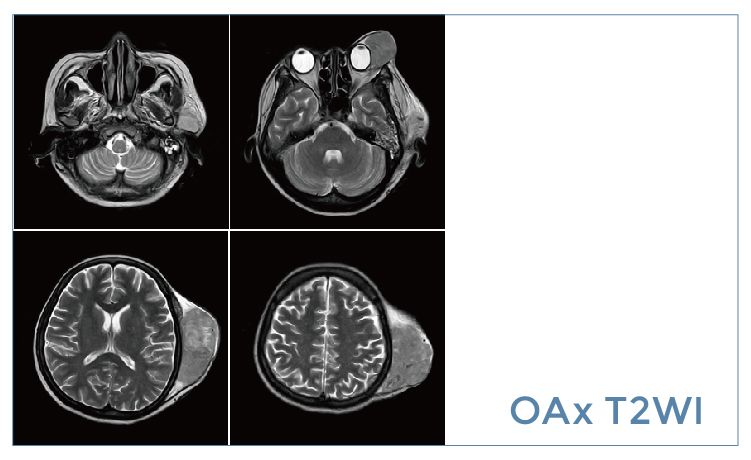

【朗润影像档案】20190920磁共振影像病例结果讨论